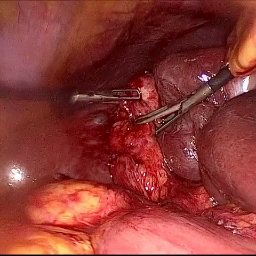

Refer to caption (a) Input Refer to caption (b) DIACMPN Refer to caption (c) Desmoke-LAP Refer to caption (d) PFAN Refer to caption (e) MITNET Refer to caption (f) Salazar Refer to caption (g) Dehamer Refer to caption (h) Ours Refer to caption (i) Target

Figure 2: Comparison of different methods on the DesmokeData dataset.

IV-C2 Qualitative Analysis

Figures 3 and 2 provide a visual comparison of the desmoking results on challenging images from the test sets. The visual results corroborate our quantitative findings. DCP not only fails to remove the dense smoke but also introduces severe color distortion. CNN-based methods like FFA-Net and MSBDN successfully remove a large portion of the smoke but tend to either leave behind a thin layer of residual haze or over-smooth the image, losing critical textural details of the tissue and surgical instruments. The Transformer-based methods, DehazeFormer and PFAN, produce significantly better results by restoring more details. However, they can sometimes struggle with non-uniform smoke distribution, resulting in regions with unnatural brightness or minor artifacts.

In stark contrast, our RGA-Net generates visually superior results that are remarkably close to the ground-truth images. It effectively removes even the densest plumes of smoke while simultaneously preserving fine-grained details, such as blood vessels, tissue textures, and reflections on surgical tools. Furthermore, the color and illumination of the restored scene appear more natural and consistent, which is a direct benefit of our model’s ability to handle both local and global features through its hybrid attention and cross-gating mechanisms. This enhanced visual clarity is crucial for improving the surgeon-robot interface in real-world clinical applications.